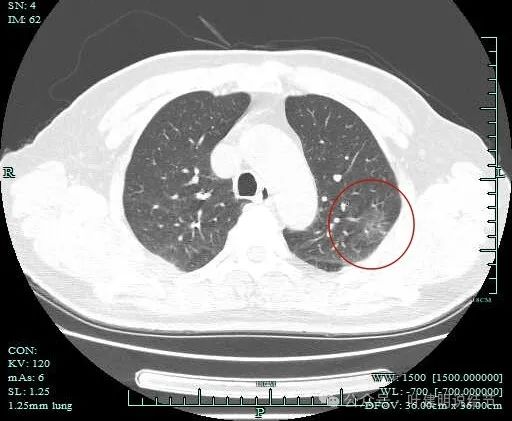

血管进入明显,且灶内端略粗于近心端。病灶内部也有血管穿行。

附近另有血管发出分支进入病灶。

明显血管穿行于灶内。

病灶距斜裂与胸肋面的胸膜都近。